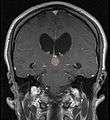

Frequently, paralysis of upward gaze along with several ocular findings such as convergence retraction nystagmus and eyelid retraction also known as Collier's sign and Light Near Dissociation (pupil accommodates but doesn't react to light) are known collectively as Parinaud's syndrome [1] or Dorsal Mid-brain syndrome, are the only physical symptoms seen. This is caused by the compression of the vertical gaze center in the midbrain tectum at the level of the superior colliculus and cranial nerve III. Work-up usually includes Neuro-imaging as seen on the right.